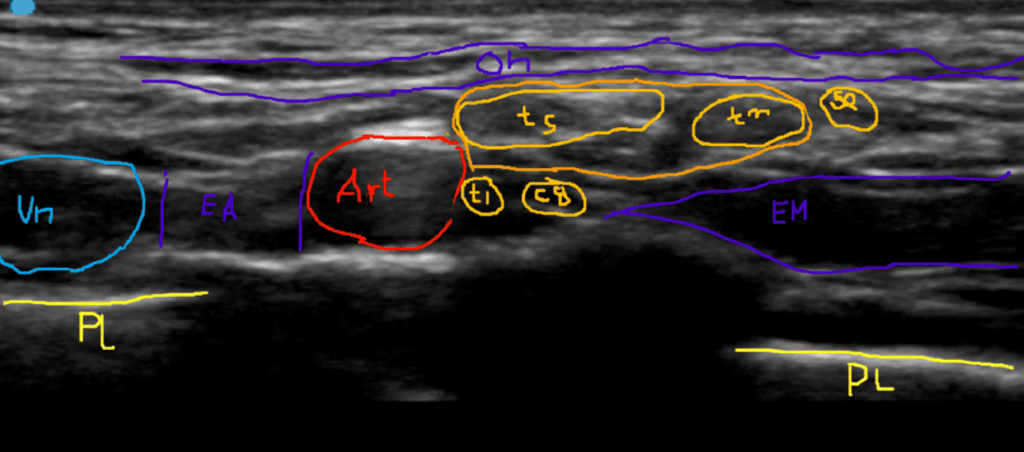

En la imagen ecográfica se muestra la arteria sobre la primera costilla, por debajo de la porción horizontal del músculo omohioideo.

Por otra parte, los troncos superior y medio dentro de la fascia que envuelve al plexo se colocan en la cara superoexterna de la arteria, junto con el nervio supraescapular.

Además, las raíces C8 y T1 (o el tronco inferior, dependiendo de la estructura y variabilidad anatómica de cada persona), se colocan en su cara interior (correspondiendo con el denominado “Corner Pocket”).

La realización de este abordaje debe de tener en cuenta la distribución del plexo a lado y lado de la arteria, tal y como veremos en la imagen a continuación.

En esta secuencia de tres imágenes se representa la imagen ecográfica del plexo en la base del cuello, es decir, el abordaje supraclavicular.

- El transductor está colocado en paralelo al borde posterior de la clavícula, apuntando en sentido caudal

- Se observa el conjunto de arteria subclavia y plexo debajo de la porción horizontal del músculo omohioideo (OH en la imagen) y por encima de la primera costilla.

- El este paciente en particular, se observan en la cara superoexterna de la arteria, los troncos superior (TS) y medio ™ envueltos por la fascia del plexo, acompañados por el nervio supraescapular (SE). En este caso, el nervio SE está empezando a separarse del plexo.

- En la cara inferior se observan las raíces C8 y T1 que justo están llegando, por esto no están todavía incluidos en la fascia ni han formado el tronco superior.

- Al lado derecho (lateral) se ve la inserción del músculo escaleno medio en la costilla (tiene aspecto tangencial por la proyección de la imagen).

- Al lado izquierdo (medial) está la inserción del músculo escaleno anterior en la costilla.

- Medial al músculo escaleno anterior se observa la vena subclavia apoyada sobre la cúpula pleural.